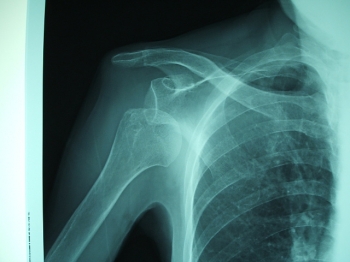

脱臼とは、「関節を構成している関節端が解剖学的状態から完全または不完全に転位して「、関節面の生理的相対関係が失われた状態」をいいます。

1位 肩脱臼

手をついたら肩が外れたなど、正常な関節に外力が働いて、生理的範囲以上の運動が強制されたときに、関節包外に飛び出たものを外傷性脱臼といいます。